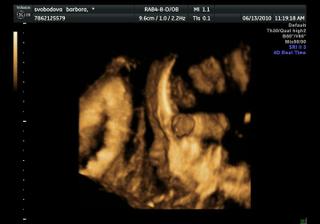

Náše bábetko a pupík🙂

Po 4 a půl letech jsme se rozhodli, že je nejvyšší čas pořídit si ten nejkrásnější dáreček 🙂 Po dvou snaženíčkách na nás vykoukly vytoužené //.